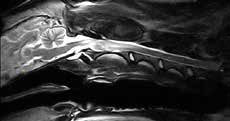

Vet-MR Grande дозволяє отримувати зображення високої якості, навіть у порівнянні з високопольними МРТ 1,5 тесла.

vet-mr-grande-4